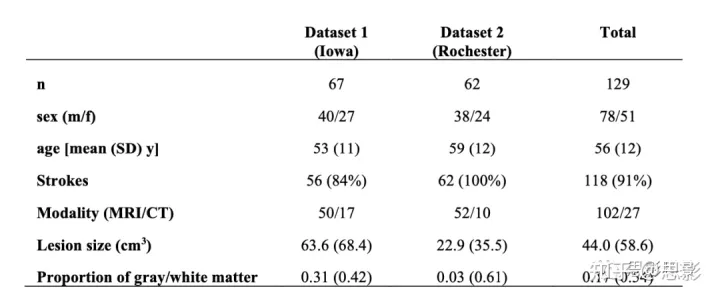

表 S1:吸烟者病变数据集的人口统计数据

每天主动吸烟被定义为在病变发作时每天吸烟超过 5 支,持续时间超过两年。在爱荷华大学队列的最初 69 名患者中,有两名患者被排除在外。在这 67 名患者中,使用 MRI 或 CT 扫描作为指导,将来自 47 名患者的病变手动追踪到模板大脑上。由于爱荷华大学的病灶追踪方法在 2006 年发生了变化,其他 20 名患者使用 FSL 在原生 T1 加权扫描上手动追踪他们的病灶,然后使用 ANTs 软件中可用的非线性配准和病灶掩蔽技术转换为 MNI152 地图集。病变掩蔽技术(Lesion masking techniques)包括对映标准化(enantiomorphic normalization),即用未受损同源物的体素强度替换病变体积,并应用成本函数对双侧病变的病变体积进行掩蔽。在本地和 MNI 空间中审查了所有病变追踪的解剖学准确性,并根据需要由其他的神经科医生进行编辑。